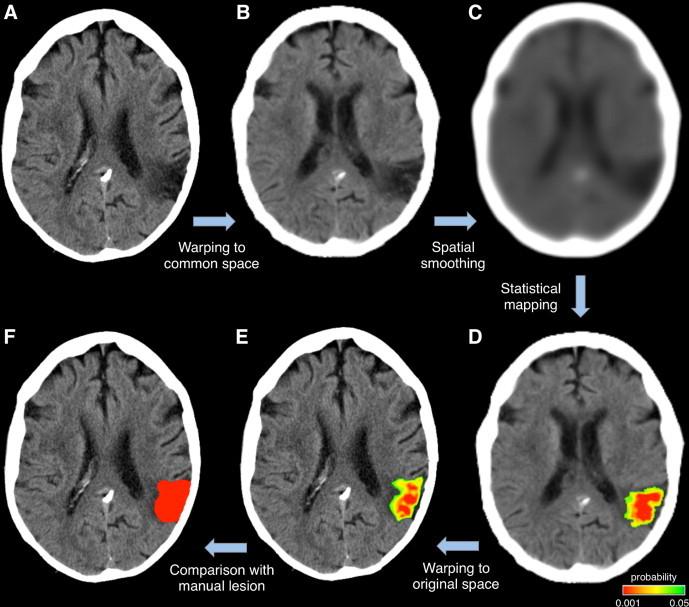

利用脑部CT图像自动勾勒中风病灶

Automated delineation of stroke lesions using brain CT images.

Computed tomographic (CT) images are widely used for the identification of abnormal brain tissue following infarct and hemorrhage in stroke. Manual lesion delineation is currently the standard approach, but is both time-consuming and operator-dependent. To address these issues, we present a method that can automatically delineate infarct and hemorrhage in stroke CT images. The key elements of this method are the accurate normalization of CT images from stroke patients into template space and the subsequent voxelwise comparison with a group of control CT images for defining areas with hypo- or hyper-intense signals. Our validation, using simulated and actual lesions, shows that our approach is effective in reconstructing lesions resulting from both infarct and hemorrhage and yields lesion maps spatially consistent with those produced manually by expert operators. A limitation is that, relative to manual delineation, there is reduced sensitivity of the automated method in regions close to the ventricles and the brain contours. However, the automated method presents a number of benefits in terms of offering significant time savings and the elimination of the inter-operator differences inherent to manual tracing approaches. These factors are relevant for the creation of large-scale lesion databases for neuropsychological research. The automated delineation of stroke lesions from CT scans may also enable longitudinal studies to quantify changes in damaged tissue in an objective and reproducible manner.

摘要

计算机断层扫描(CT)图像被广泛用于识别中风后梗死和出血导致的异常脑组织。目前手动勾勒病变是标准方法,但既耗时又依赖操作人员。为了解决这些问题,我们提出了一种能够自动勾勒中风CT图像中梗死和出血区域的方法。该方法的关键要素是将中风患者的CT图像准确归一化到模板空间,并随后与一组对照CT图像进行逐体素比较,以确定信号强度减低或增高的区域。我们使用模拟病变和实际病变进行的验证表明,我们的方法在重建梗死和出血导致的病变方面是有效的,并且生成的病变图在空间上与专家操作人员手动生成的病变图一致。一个局限性是,相对于手动勾勒,自动方法在靠近脑室和脑轮廓的区域灵敏度降低。然而,自动方法在节省大量时间以及消除手动追踪方法固有的操作人员间差异方面具有诸多优势。这些因素对于创建用于神经心理学研究的大规模病变数据库具有重要意义。从CT扫描中自动勾勒中风病变还可能使纵向研究能够以客观且可重复的方式量化受损组织的变化。